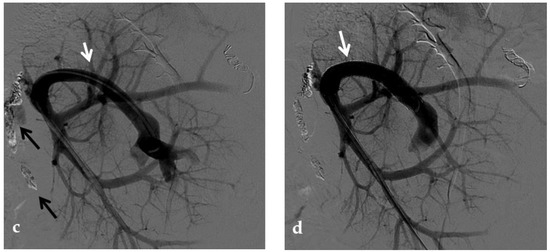

Figure 9.

Anteroposterior view of a percutaneous transhepatic portography imaging series performed for chronic complete portal vein thrombosis with cavernous transformation in an 11-year-old boy with a history of gastrointestinal bleeding and portal hypertension 10 years after deceased-donor orthotopic liver transplantation (split II–III) for biliary atresia. (a) Portography image shows a regular representation of the segment 3 portal branch, while the segment 2 portal branch has a peripheral defect of opacification due to flow reversal, resulting from portal cavernoma and extrahepatic capsular feeding from gastric vessels (black arrow). Complete occlusion of the extrahepatic portal vein at the hepatic hilum (white arrow) is demonstrated. (b) Portography image shows the opacification of a very tiny vascular structure (arrow) which represents what remains of the thrombosed extrahepatic portal trunk. (c) Fluoroscopy image shows angioplasty with a non-compliant 8-mm balloon catheter performed on a stiff guidewire which was advanced across the obstructed tract. (d) Control portography shows a re-expanded extrahepatic portal vein (arrow) with normal spleno-portal opacification. Portal vein thrombosis recurred one year after treatment and required repeated angioplasty and metal stenting (shown in the next figure).

No consensus exists regarding the optimal indication for stent placement in PVT. Portal vein stent placement seems to be a safe and effective method for the treatment of post-transplantation PVT in pediatric recipients. The intermediate-term portal vein patency after stent placement is excellent [70] (Figure 10). In one study, after recanalization of the segment of portal vein affected by thrombosis through PTA, if an elastic recoil of more than 50% of the normal extrahepatic portal vein, a residual pressure gradient of more than 5 mmHg or a vascular dissection were found, stent placement was performed [8]. Several other investigators have reported a 100% portal vein patency rate after stent placement with various follow-up times [71,72]. These patency rates are superior to those previously reported with balloon angioplasty alone (27–50%) [73].

Figure 10.

Anteroposterior view of a percutaneous transhepatic portography imaging series in the same patient as in Figure 9. (a) Portography image shows recurrence of complete extrahepatic portal vein thrombosis (white arrow) 1 year after the first angioplasty treatment. Flow reversal in the segment 2 portal branch resulting from portal cavernoma is still evident (black arrow). (b) After transhepatic portal vein recanalization with the angiographic catheter, the splenic portogram shows jejunal cavernoma (white arrows) and gastric (black arrow) varices, due to complete obstruction of the extrahepatic portal trunk. Embolization of varices was performed using a mixture of N-butyl cyanoacrylate and iodized oil and metallic coils. (c) Portography image after angioplasty of the extrahepatic portal vein shows successful endoluminal filling of the portal vein, with a restored but still irregular profile (white arrow). Note subtraction artifacts (black arrows) representing lipiodol and coils in the cavernoma and varices. (d) Final portogram performed after deployment of a 10-mm self-expandable bare metal stent to treat residual stenosis of the extrahepatic portal vein; the main portal vein is now regularly opacified with adequate size and both intrahepatic portal branches present hepatopetal flow.